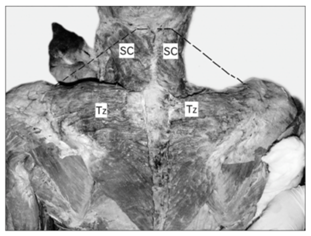

Emsley et al.12 have reported a morphological anomaly found during a cadaverous dissection on a 89year-old subject. The left trapezius was significantly smaller than the right trapezius, especially in its caudal part. They also noted that the muscle fibers of the left trapezius were much lighter than on the right. Moreover, the existing fibers of the left trapezius inferior to the scapula were only one-third to two-thirds as thick as those on the right. The vertebral attachment of the inferior fibers of the left trapezius was also notably higher than that on the right. Morphometric analysis indicated that the surface area of the left trapezius was approximately 50% that of the right trapezius. In addition, the orientation of the fibers was different (Figure 2).

Figure 2 A: Dissection of the back and neck showing absence of cervical part of trapezius. Dotted black line depicting the normal extent of the cervical part of trapezius. SC: Spleniuscapitis; Tz: Trapezius.

B: Muscles undercover of trapezius seen after reflecting it laterally. LS: Levatorscapulae; Rh: Rhomboides; Tz: Trapezius [10].